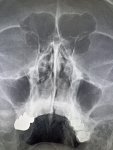

Здравствуй двачик, на прошлой неделе вышел из отпуска и уже дергается глазик, вчера сидел на работке пока поликлинику не закрыли и не все доделал. Не могу перестать кричать внутри головы! Потому мы с вами будем сегодня играть в доктора! Я буду вам показывать фоточки а вы угадывать пиздецомы! Што шпогнали! Найдите поломку!